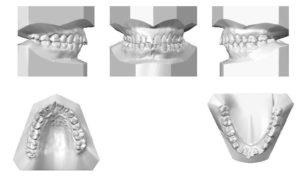

5. Gipsovka modell záró

Abban az esetben, lepecsételt koronák modellek általában gipsz okkiúdert. Articulator túl drága és bonyolult az ilyen típusú koronák.

Gipsz modell nagyon egyszerű. A modell a felső állkapocs öntjük egy kis vakolat, ragasztott a felső bilincs okkiúdert. Ezután az alsó állkapocs modell szerelt centrikus kapcsolatban. És ilyen helyzetben van ragasztva az alsó bilincs oklyudatora.